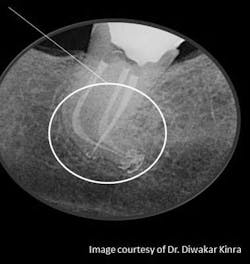

Characteristics of well-done obturation are defined and categorized as the three-dimensional filling of the entire root canal system as close to the cemento-dentinal junction as possible; i.e., without gross overextension or underfilling in the presence of a patent canal. Minimal amounts of root canal sealers — most of which have been shown to be biocompatible or tolerated by the tissues in their set state — are used in conjunction with the core filling material to establish an adequate seal. However, it is only through a knowledgeable approach to root canal treatment that quality assurance can be continually demonstrated in the obturation of the canal system. (7)